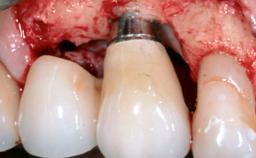

Despite anti-infective surgical treatment, some patients may experience recurrent infection and progressive bone loss requiring additional treatment. Removal of Implant Due to Recurrent Infection describes a conservative approach using an implant retrieval tool without the need for excessive bone removal or use of a trephine.

A 70-year-old female patient was referred by her general dentist to the periodontist for assessment and management of an infection associated with implant 36. The general dentist had noted suppuration on probing during examination.